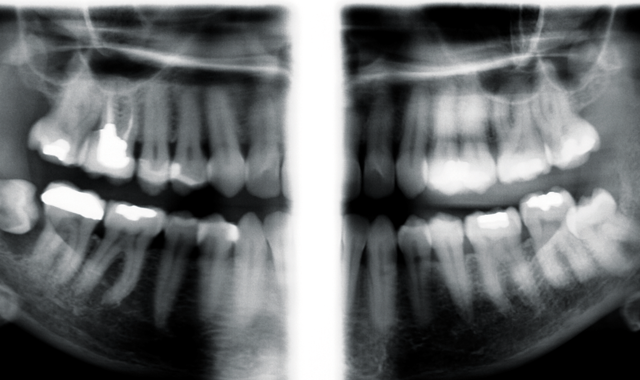

Further examination was deemed necessary, but instead of conducting more intraoral bitewing X-rays, extraoral bitewings were discussed with the patient. Again, taking into consideration the patient’s radiophobia, the adjustable mA and kV would allow the optimal radiation dose, while adhering to the ALARA (As Low As Reasonably Achievable) principle. The benefit to the patient would be that extraoral bitewing X-rays would provide the necessary imaging with a substantial reduction in radiation exposure versus taking four intraoral bitewing X-rays to cover the same area in question-thus helping to ease the patient’s concern regarding exposure to radiation.

Planmeca extraoral bitewing follow up X-rays were taken in 2015, utilizing Planmeca’s exclusive robotic SCARA (Selectively Compliant Articulated Robot Arm) technology. As a result, additional periapical regions, including the 3rd molar areas, were now able to be included in the images.

Image of Planmeca extraoral bitewings

From the expanded regions available via extraoral bitewings X-rays, the cyst around the #32 tooth was discovered. The patient was informed of the need to have the wisdom tooth removed, and the possibility of damage to the inferior alveolar nerve and permanent paresthesia.